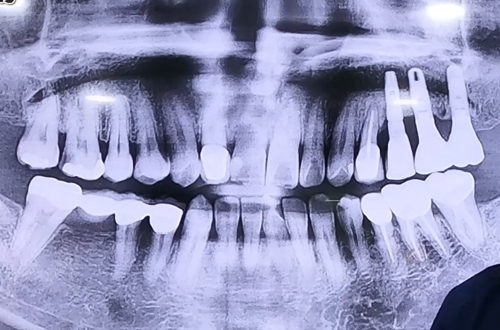

AFTER

상한 치아를 빼시고 그 자리에 바로 임플란트를 심은 뒤,

빈 공간을 뼈이식으로 단단히 채워주고 보호를 위해 덮개를 덮어 마무리해 드렸습니다.

환자분은 임플란트가 단단히 붙어 자리 잡을 때까지 4개월 정도 기다린 후

다음 치료를 진행할 예정이며, 치아가 완성되면 다음 진료일지로 찾아뵙겠습니다. ^^